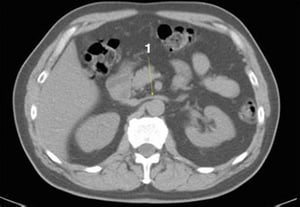

CT-Scan von Abdomen und Becken mit normaler Anatomie ohne Kontrastmittel (Folie 13)

1 = V. mesenterica superior; 2 = A. mesenterica superior.

© Springer Science+Business Media